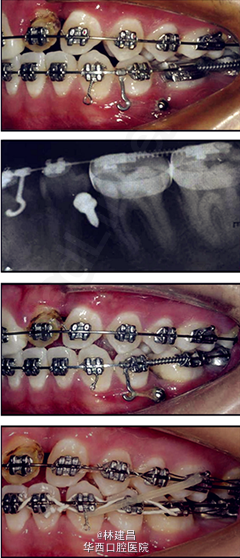

患者为18岁男性,面形凹,上颌骨发育不足,有一处重度牙槽突裂,因面部不美观,来正畸科求治。综合评价其病情后,为患者提供了手术和非手术两种方案,患者最终决定了非手术方案。此后患者的正畸治疗包括了扩弓、拔牙和牙周修复会诊。正畸治疗使用了新亚MBT托槽0.022x0.028(国产托槽也有好货!)配合微种植钉,排齐整平恢复I类磨牙关系。治疗完成1年后复诊。